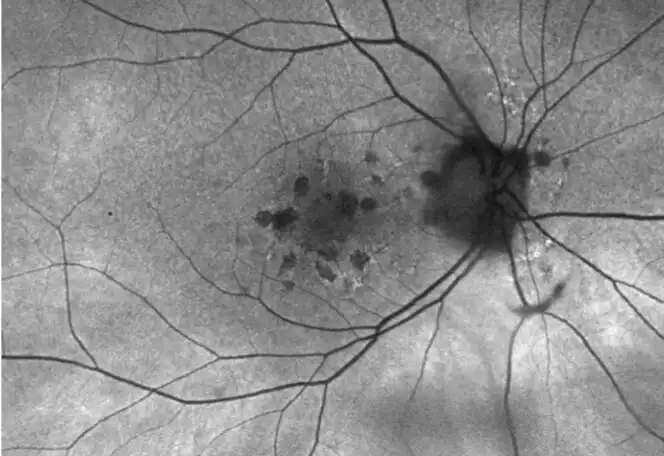

IZERVAY™ (avacincaptad pegol intravitreal solution) is indicated for the treatment of geographic atrophy (GA) secondary to age-related macular degeneration (AMD)